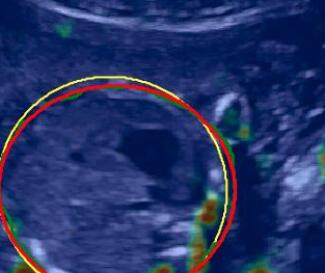

The proposed method generally outperforms the baseline and the proposedAG method, thus we only integrate the shadow confidence maps generated by the proposed method () into the weighting strategy in [39]. In detail, the probability value of each pixel in a shadow confidence map is multiplied to the original weight of the same pixel computed in [39]. The generated new weights are normalized as described in [39] and then are used for image fusion. The data set in this experiment is same as used for [39].

Fig. 9 qualitatively shows that shadow confidence maps are able to improve the performance of US image fusion algorithms with different weighting strategies. Fig. 9 also shows the difference between adding two different types of confidence maps. These two types of confidence maps are generated by the confidence estimation network which are separately trained by either MSE or Sigmoid loss. Fig. 9 (a) to (d) illustrate image fusion results for the same case using different combinations of weighting strategies and loss functions. The difference maps indicate that shadow confidence maps are capable of improving image fusion performance. Fig. 9 (e) to (h) show image fusion results on four different cases. We randomly select two positively affected cases (Fig. 9 (e) and (f)) to show visual improvement. We additionally show two randomly selected examples (Fig. 9 (g) and (h)) that don’t show perceptually significant improvements after adding shadow confidence maps. Quantitative evaluation for image fusion is not possible because of lacking a ground truth for US compounding tasks.